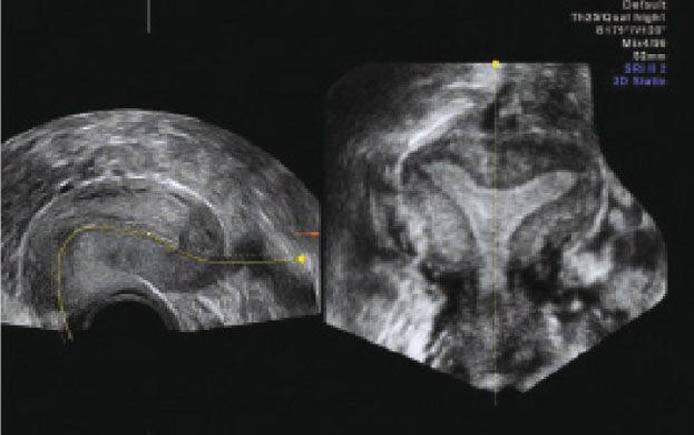

На изображениях можно увидеть, как выглядит данная аномалия.

Матка седловидной формы диагностируется только с помощью инструментальных исследований. А именно:

- Ультразвукового исследования (УЗИ). Определяется, таким образом, отклонение не во всех случаях. В основном результативно тогда, когда дама в положении. Чтобы такой метод был информативным, то лучше использовать вагинальное УЗИ во 2-ой фазе цикла. Специалист будет использовать вагинальный датчик, на который предварительно наденет одноразовый презерватив.